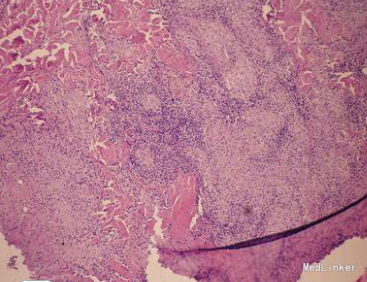

查体:一般情况良好,生命体征正常,全身浅表淋巴结未触及肿大,心肺及腹部检查无异常。皮肤科检查:右耳切除处见红褐色浸润性斑块,触之柔软,界限清楚,融合成大瘢痕。实验室检查:血常规、尿常规、肝肾功能均正常,胸部X线检查无异常;结核菌素试验强阳性(硬结直径超过20 mm)。血红细胞沉降率升高。皮损真菌培养阴性,快速血浆反应环状卡片试验(RPR)及梅毒螺旋体血凝试验(TPHA)均为阴性。皮损病理检查显示:表皮棘层肥厚,角化过度乳头瘤样增生,真皮浅层弥漫性淋巴细胞、中性粒细胞浸润。其中可见结节样的上皮样细胞和多核巨细胞,中央可见干酪样坏死。皮损分泌物通过分枝杆菌培养4周阳性,菌型鉴定为结核分枝杆菌。

皮肤结核是结核分枝杆菌侵犯皮肤或其他脏器,结核病灶累及皮肤引起的皮肤损害,可迁延数年或数十年之久。如果治疗不及时,可能留下损毁性瘢痕。寻常狼疮是一种慢性进行性皮肤结核病,病程可长达数十年。病损常缓慢扩大,可波及大片皮肤,损坏鼻、耳、口唇、眼睑等处,形成瘢痕甚至毁容等。患者的皮损表现为孤立浸润性斑块及结节,结合皮损组织病理检查可确诊为皮肤结核(寻常狼疮)。